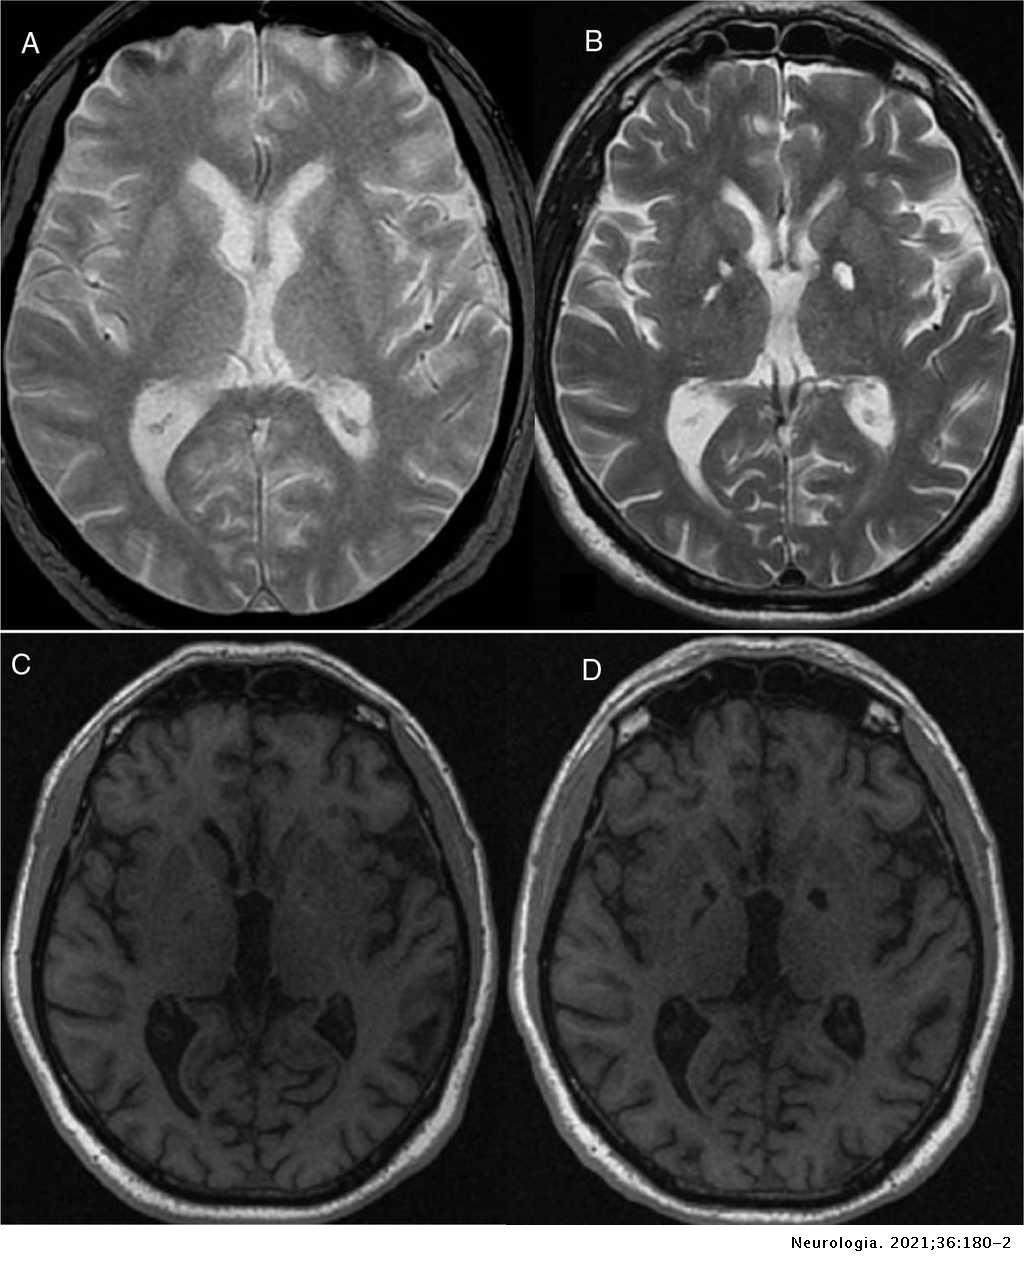

The person is conscious but in a state of profound apathy and unaware of or insensitive to. Hypoactive-hypoalert behavior HHB also termed psychic akinesia is characterized by loss of psychic autoactivation apathy and stereotyped activity that are reversed by external stimulation1 Lesions in the brainstem basal ganglia or frontal lobes can underlie HHB1 We report three patients presenting with HHB due to spontaneous.

Hypoactive Hypoalert Behavior Psychic Akinesia In Intracranial Hypotension Syndrome Neurology

Abulia also known as apathy psychic akinesia and athymia refers to a lack of will drive or initiative for action speech and thought and is felt to be related to dysfunctions with the brains dopamine-dependent circuitry. A CT scan disclosed bilateral low density lesions involving the pallidum. Psychic akinesia This fourth phase is one of the most serious increasing the previous symptomatology in such a way that although there is consciousness there is a total lack of sensitivity.